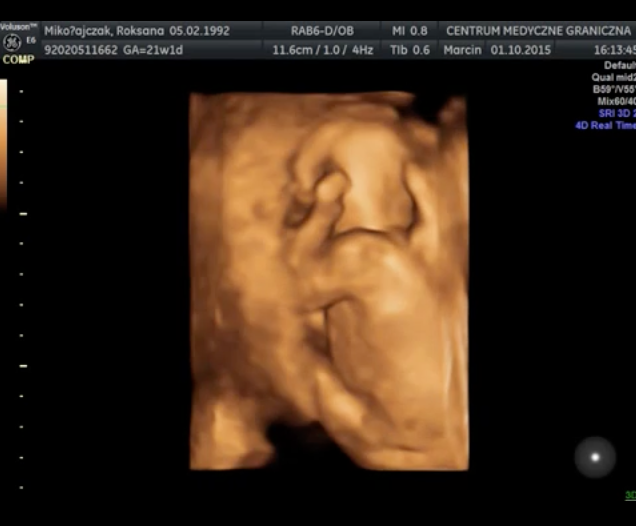

Wyniki badań prenatalnych są bardzo dobre. Obecnie trwa 23 tydzień ciąży, a mała waży 500 gram. Lekarz zalecił mi jednak kontrolę przepływu krwi, ponieważ obecne wyniki mieszczą się w górnej granicy normy 101cm/s. Wykonanie USG nie było wcale takie proste – maleńka Kasia jest bardzo ruchliwa i nie pozwalała się zmierzyć podczas badania. W czasie jego trwania udało się nagrać kilka krótkich filmów i zdjęć, możecie je zobaczyć poniżej. Kolejne badanie prenatalne odbędzie się 10-go grudnia. Termin porodu wyznaczono na 11 lutego i prawdopodobnie odbędzie się za pomocą cesarskiego cięcia.